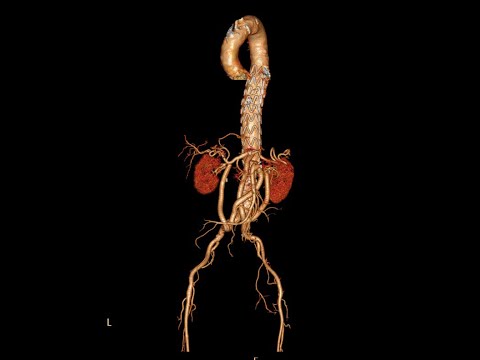

A 62/M COPD pt with Type 5 TAAA under went Hybrid TEVAR. Link for surgery in this link -youtu.be/cVKjV5J8YFk